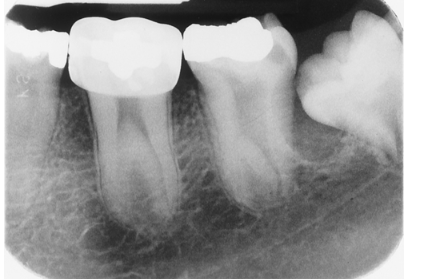

Note the occlusal anatomy of the occlusal surface of the mandibular 2nd molar that has just erupted. Now look at the maxillary 2nd premolar and lower premolars. What is your assessment of these teeth?

enamel hypoplasia

rampant caries

dentin dysplasia

Don't look at me, I don't diagnose.